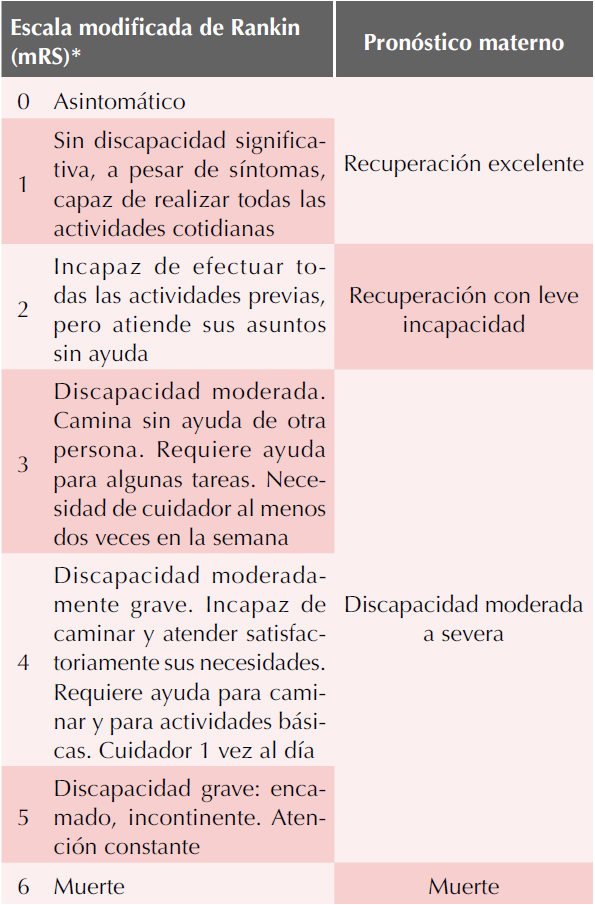

La resonancia magnética, en venorresonancia, mostró: trombosis en el primer tercio del seno lateral transverso izquierdo (Figura 1). Se indicó tratamiento anticoagulante con enoxaparina, a dosis terapéuticas y 2 mg/día de acenocumarol por vía oral. Dos días después del inicio de los anticoagulantes los controles bioquímicos mostraron: prolongación del International Normalized Ratio (INR) (1.66, 0.8-1.2) y TP (20.7, 11.1-16). La paciente permaneció estable en las cifras tensionales y la cefalea fue disminuyendo gradualmente, hasta encontrarse asintomática. Se dio de alta por mejoría y con un puntaje en la escala de Rankin modificada2 de 0 (Cuadro 2). El quinto día de estancia intrahospitalaria, décimo tercero del puerperio, recibió nifedipino de liberación prolongada a la dosis de 60 mg/día, 100 mg/día de metoprolol y 2 mg/día de acenocumarol por vía oral.

Cuadro 2 Escala modificada de Rankin, con pronóstico materno después de un evento de trombosis venosa cerebral

* Cantu-Brito C, Arauz A, Aburto Y, et al. Cerebrovascular complications during pregnancy and postpartum: Clinical and prognosis observations in 240 Hispanic women. Eur J Neurol 2011;18:819-25.